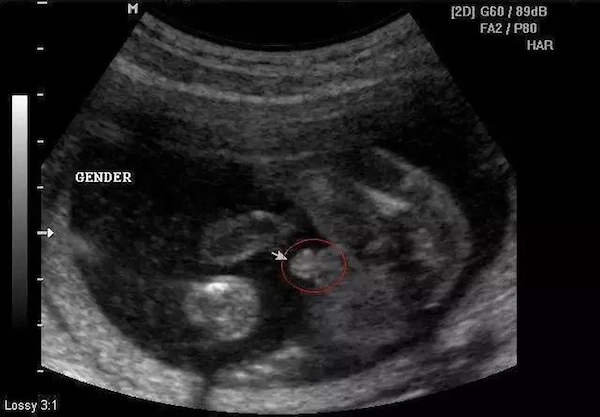

B超能看到性别,得等到长出外生殖器

超声看到的是形态上的影像,当胎儿的外生殖器长到可以通过超声看到的程度,就可以进行检查了。一般需要怀孕3-4月以后了,不过误差也比较大。更何况,我们国家法律明令禁止孕期看性别,所以,你就别想啦。

圈圈示意